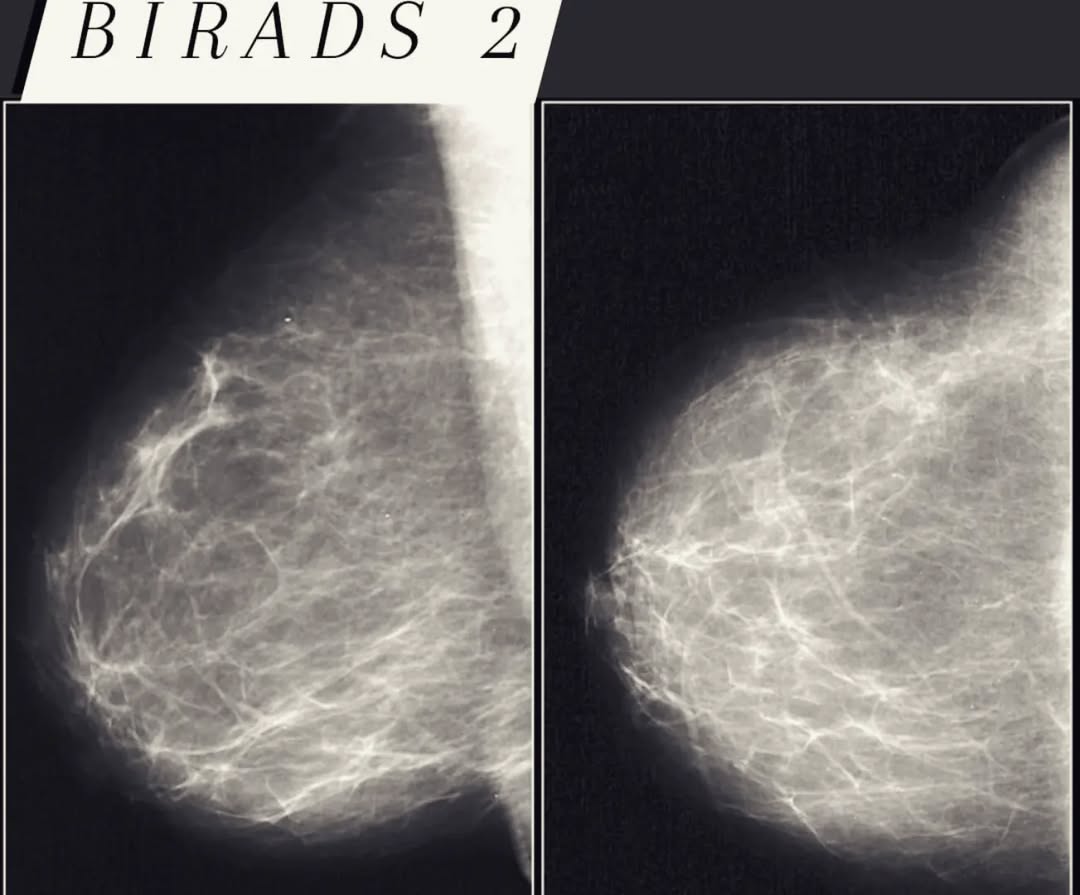

• BIRADS 2 – Benigne (dobroćudne) promene, bez potrebe za daljim praćenjem.

Na primerima mamografskih pregleda možete videti kako BIRADS klasifikacija funkcioniše u praksi.